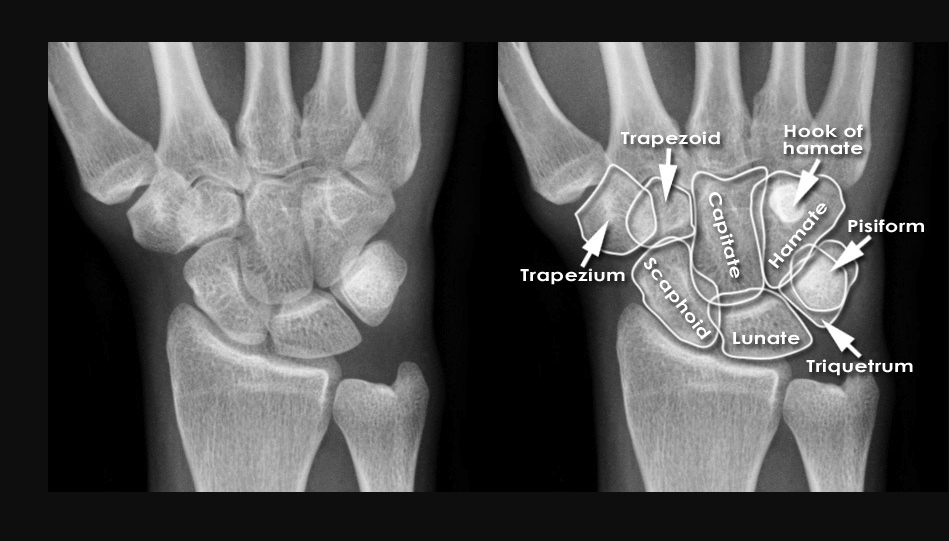

What are the bones of the hand?

What is the abnormality seen in the XR below? Management?

Scapholunate dissociation

THUMB SPICA SPLINT

Ortho follow up